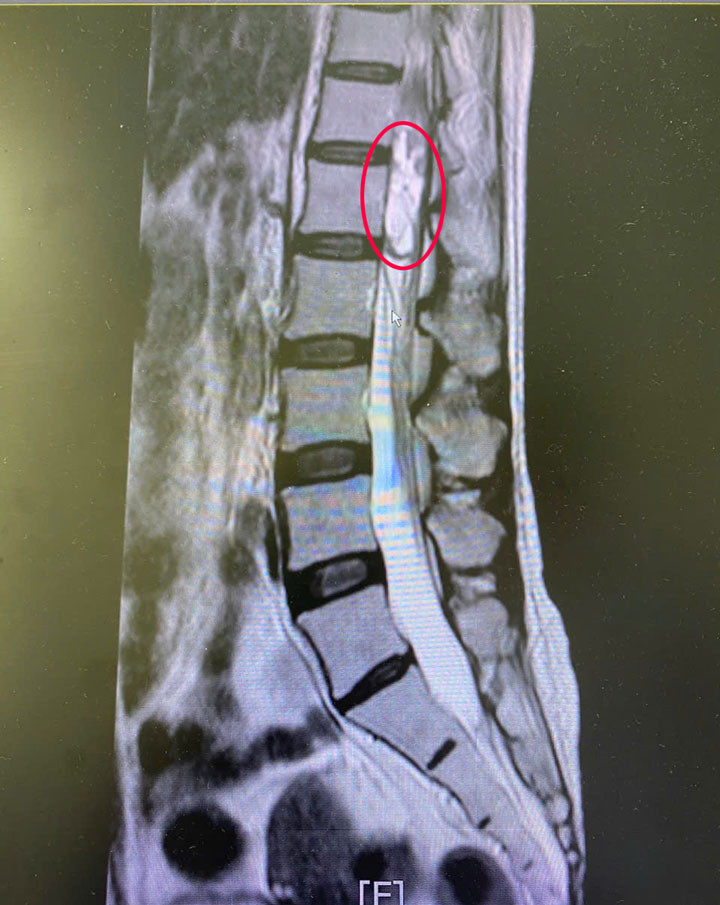

| Khối u tủy sống của người bệnh (vùng khoanh tròn màu đỏ) |

Bằng kinh nghiệm và làm chủ kĩ thuật, kíp phẫu thuật đã thực hiện ca phẫu thuật nhanh chóng, chính xác, bóc tách thành công khối u tủy sống kích thước lớn 5x1cm, bảo vệ an toàn cấu trúc tủy sống và rễ thần kinh.